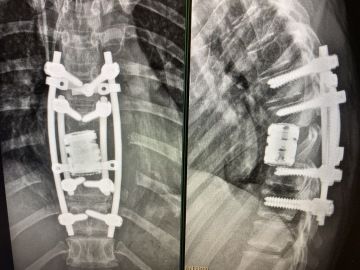

V létě 2023 jsem začala trpět bolestmi zad. Na jaře mi snížili invalidní důchod, takže jsem v kavárně již pracovala. Myslela jsem, že je to tím - víc pohybu, jiný režim,… Postupně ale přicházely dny, kdy jsem sotva vstala z postele. Klidové bolesti, které jsem už dobře znala. Podvědomě jsem tušila, ale přiznat si to bylo moc těžký. Kontrola v srpnu mé nejhorší obavy potvrdila. Metastáza v páteři. Byla to asi největší beznaděj, jakou jsem dosud cítila. Hlavou se mi honilo, že už se s Enie neprojdu a jak mi bude naše toulání chybět. Na kontrolní celotělové scintigrafii před operací se odhalila ještě jedna metastáza. Ve stehenní kosti. Následovalo čekání na rozhodnutí spondylochirurgů, jestli budou vůbec operovat. Věděla jsem, že pokud do toho nepůjdou, nečeká už mě pěkná cesta. Mezitím ortopedi rozhodli, že stehno odoperují zhruba měsíc po operaci páteře, pokud se uskuteční. A i když Brno nemám od začátku zrovna v lásce, musím říct, že lepší doktory bych si snad ani nemohla přát. A tak jsem 1. září v půl sedmé ráno usínala na operačním sále a jen doufala, že se operace podaří. Probrala jsem se po páté odpoledne na JIP a upřímně, nezažila jsem větší bolest. Byl mi nahrazen obratel a stabilizace sahá přes další čtyřiobratle. Tři týdny v bolestech, ale ten čtvrtý jako zázrakem bylo po. Bez bolestí jsem se s Jirkou a Enie vydávala denně na procházky, abych si každou chvíli s nima venku užila naplno. Protože 5. října už jsem ležela na operačním sále znovu. Tahle operace nebolela ani zdaleka tolik jako ta předchozí, co ale bolelo byl následující rok o berlích. Od listopadu jsem ještě podstoupila ozařování páteře, protože histologie nepotvrdila čisté resekční okraje. A následně jsem denně začala užívat udržovací chemoterapii v tabletách. Další kontroly v roce 2024 vycházely krásně, čistě. V hlavě jsem ale stále bojovala s berlemi. Ale měsíce utíkaly.